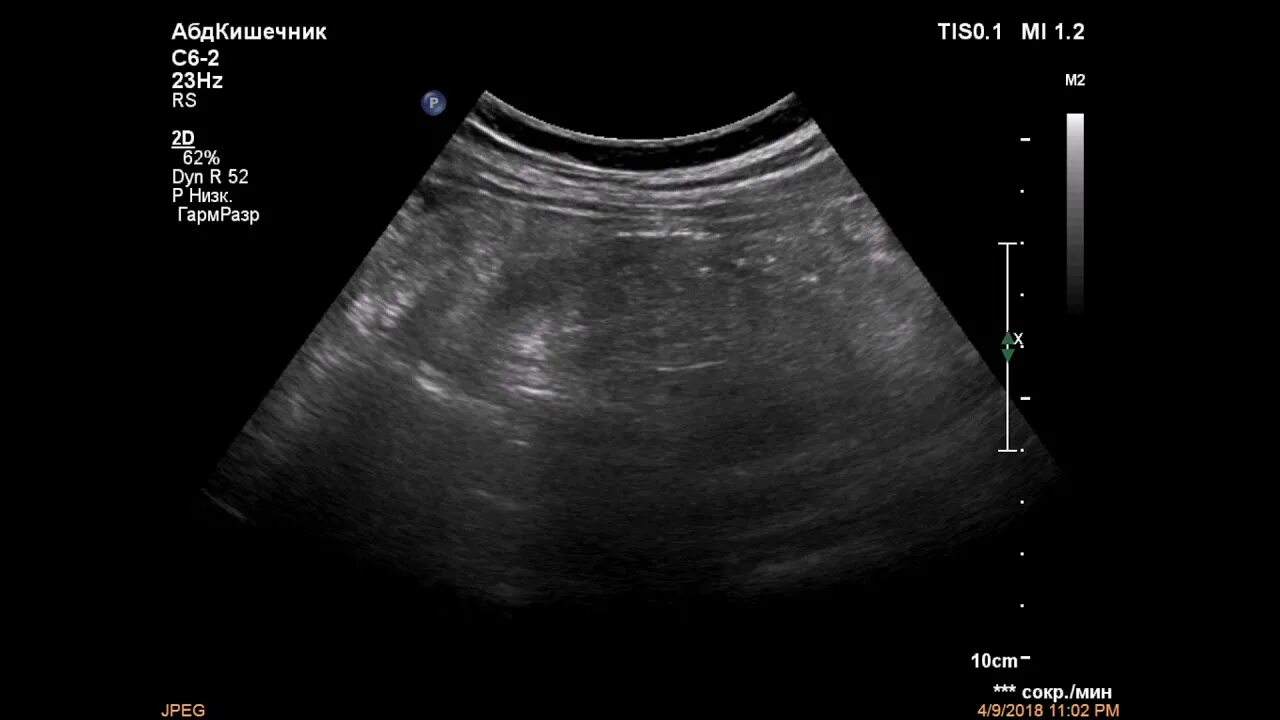

Какое узи при аппендиците